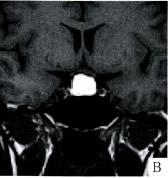

诊断:Rathke囊肿伴出血。

3. 定性诊断:年轻女性,鞍内见囊性占位,边缘光滑、清楚,应考虑为良性病变。向鞍上生长,却未见“束腰征”,病灶大部分T1WI及T2WI均呈高信号,应考 虑几种可能,含脂肪、黏蛋白或亚急性出血,脂肪抑制仍为高信号,脂肪可排除。信号欠均匀,可见低信号液平,考虑有出血存在。病灶主要成分含黏蛋白可能性较 大,增强后病灶无强化,未见明显垂体组织强化,考虑Rathke囊肿可能性最大。本例经病理(图G)证实为:Rathke裂囊肿出血。

4. 鉴别诊断:本例囊液T1WI、T2WI均为高信号,须排除脂肪信号或亚急性出血,前者压脂序列信号明显减低,后者应在短期内随访病人,观察病变信号变化, 可作出正确的诊断。本例应与几种鞍内囊性病变相鉴别:①垂体瘤卒中:T1WI、T2WI均表现为高信号,易与以T1WI高信号特征的Rathke囊肿相混 淆,垂体肿瘤的“束腰征”为其特征;②颅咽管瘤:多呈分叶状,伴有钙化,而Rathke囊肿无钙化,增强后前者囊壁和实性部分有强化;③鞍区蛛网膜囊肿: 单纯鞍区蛛网膜囊肿极为少见,多位于鞍上或鞍旁,MRI信号强度与脑脊液相似,增强扫描不强化,受压变扁的垂体组织可见强化。